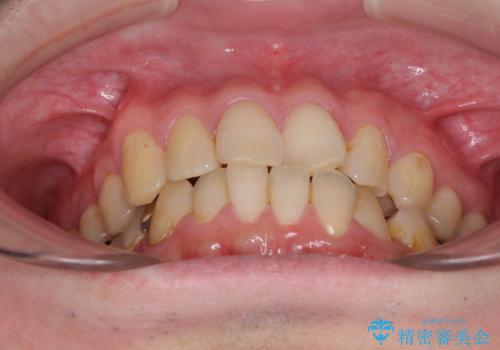

- デコボコした前歯をセラミックできれいに揃えたいとのことで来院された患者様です。

歯を削って整えることは簡単ですが、健全な歯を削って後悔してからでは遅いため、矯正治療を提案しました。

はじめは矯正治療の期間が長いことに悩んでいらっしゃいましたが、ある程度整えば満足するだろうとのことで、インビザラインにて矯正治療を行うこととしました。

左上の犬歯が欠損しているため、正中の位置や奥歯の咬み合わせが理想的にならない点を了承していただきました。